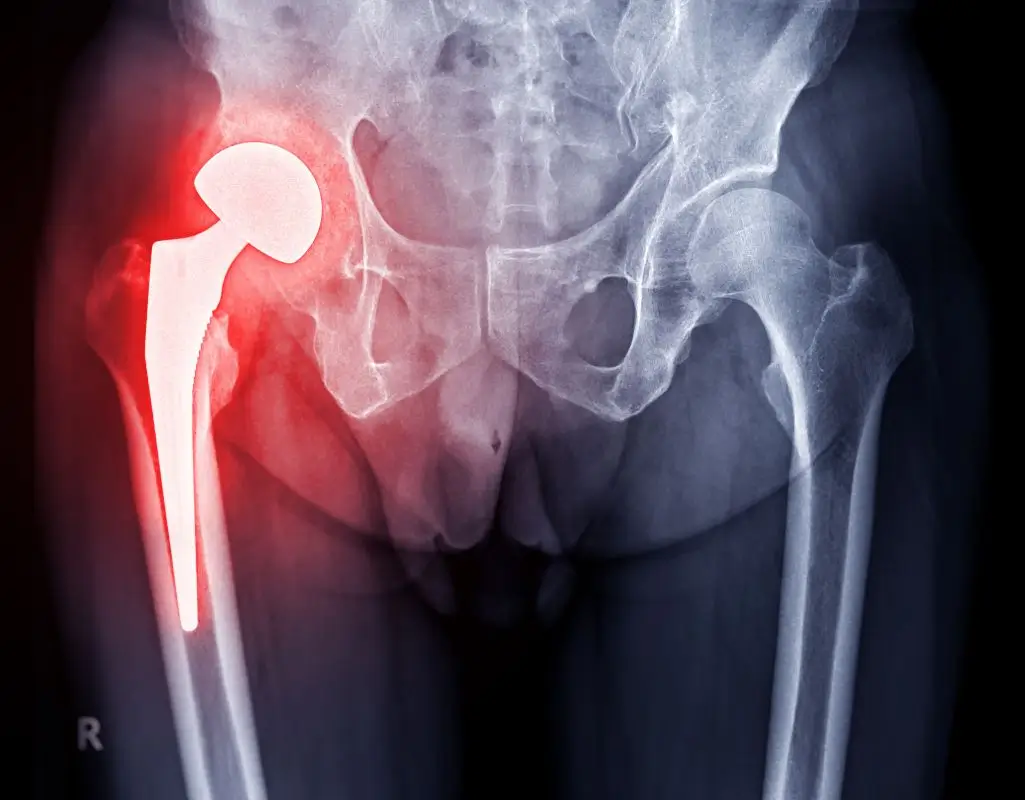

Ból bioder może pojawić się nagle, po dłuższym spacerze, treningu albo przy wstawaniu z łóżka. Bywa to lekki dyskomfort, ale czasami utrudnia nawet założenie butów czy swobodne poruszanie się. Choć łatwo go zignorować, właśnie takie sygnały mówią, że Twój staw biodrowy wymaga uwagi. Na szczęście dzięki nowoczesnym metodom medycyny regeneracyjnej możesz uniknąć operacji. Jedną z najskuteczniejszych i najbezpieczniejszych form terapii jest leczenie bioder z zastosowaniem osocza bogatopłytkowego (PRP). W tym tekście pokazuję, na czym ta metoda polega i dlaczego warto ją rozważyć, gdy zmagasz się z bólem biodra.

Osocze bogatopłytkowe (PRP) to koncentrat płytek krwi pozyskiwany z Twojej własnej krwi. To właśnie płytki krwi zawierają aktywne czynniki wzrostu, które uruchamiają procesy regeneracyjne w Twoim organizmie. Kiedy podaje się osocze w okolicę uszkodzonego stawu biodrowego, odbudowują się ścięgna, więzadła, chrząstka i błony maziowe.

Wiele osób cierpiących na ból biodra doświadcza przeciążeniowych zapaleń ścięgien, stanów zapalnych kaletek maziowych czy zmian zwyrodnieniowych. Trudno je wyleczyć, bo uszkodzone tkanki regenerują się powoli. Tu właśnie sprawdza się osocze bogatopłytkowe.

Gdy wstrzyknie się je bezpośrednio w okolice uszkodzonych struktur, przyspiesza odbudowę i często już po pierwszym zabiegu zauważysz zmniejszenie bólu i lepszą ruchomość. W zależności od stopnia zaawansowania problemu konieczne może być 1–3 podań w kilkutygodniowych odstępach.